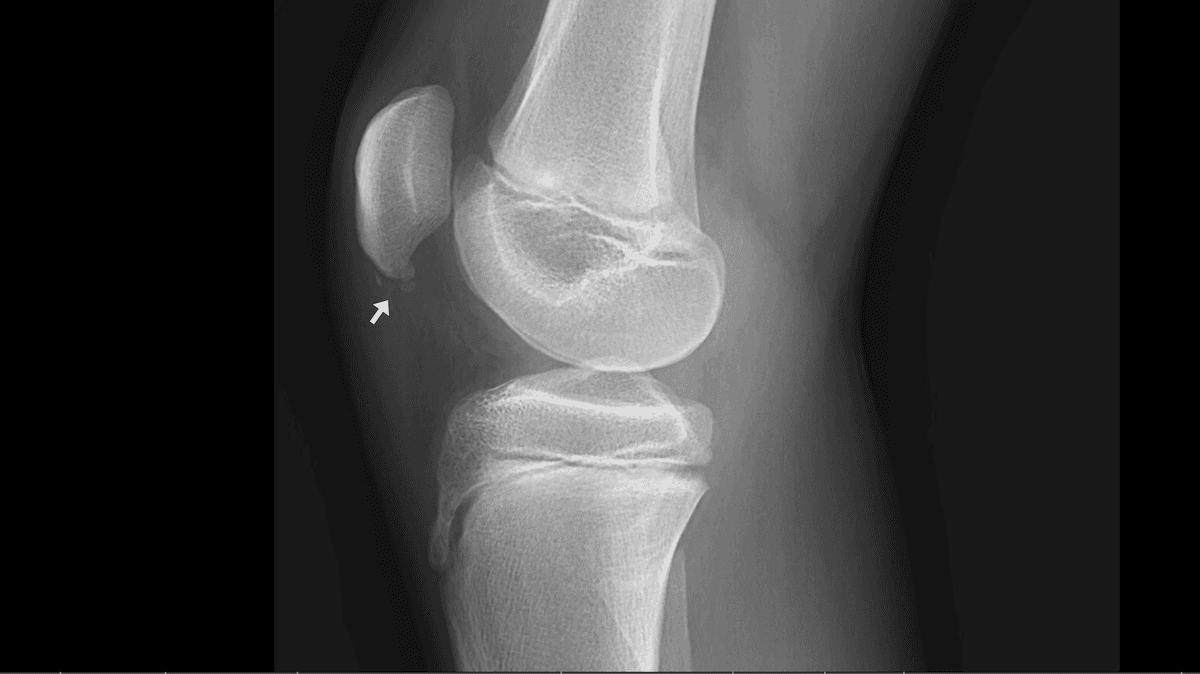

Ostéochondrose apophysaire proximale du tendon patellaire chez un adolescent de 15 ans pratique le basket.

RX